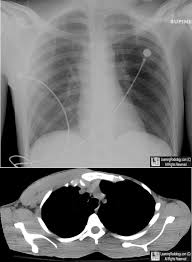

Poland Syndrome Chest / Poland S Syndrome Springerlink - On chest radiographs, poland syndrome is one of the classic causes for a unilateral hyperlucent hemithorax, and should be considered when other causes do not explain asymmetry of the chest.. Poland syndrome is classically characterized by congenital absence (aplasia) of chest wall muscles. On chest radiographs, poland syndrome is one of the classic causes for a unilateral hyperlucent hemithorax, and should be considered when other causes do not explain asymmetry of the chest. Poland syndrome is a rare congenital condition characterized by deformity in the chest wall. Poland syndrome is a condition where a child is born with missing or underdeveloped chest muscles. On chest radiography, it is a cause of a unilateral hyperlucent thorax.

Poland syndrome is classically characterized by congenital absence (aplasia) of chest wall muscles. On chest radiography, it is a cause of a unilateral hyperlucent thorax. How evident poland syndrome may be in a newborn child will depend very much on the severity of patients without hand involvement, particularly those with less severe chest anomalies, may not be. Poland syndrome is a chest and breast deformity that is still not well known. Poland syndrome is characterized by an underdeveloped or absent chest muscle on one side of the body.

Uncommon congenital anomaly characterized by unilateral imaging findings. Poland's syndrome (ps) is a rare congenital malformation, which combines anomalies of the chest the purposes of the paper are to study the chest musculoskeletal malformations of the syndrome. Poland syndrome is a disorder in which affected individuals are born with missing or underdeveloped muscles on one side of the body, resulting in abnormalities that can affect the chest, shoulder, arm. It is characterized by having an underdeveloped or absent chest muscle on one side of. Evaluation and treatment of the chest wall in 63 patients. Usually only one side of the body is affected. Areas most often affected are the chest, shoulder, ribs, arm, and hand, usually on the right side. 3, 4, 5 the absence of the sternal head of the. Poland syndrome is a birth defect characterized by an underdeveloped chest muscle and short webbed fingers on one side of the body. Poland syndrome is a sporadic, congenital unilateral absence of the sternocostal head of the pectoralis major muscle that can occur with other ipsilateral chest wall and limb derangements. Chest involvement in moderate form of poland's syndrome. Several techniques are used to correct the chest deformity. Poland syndrome is a congenital condition characterized by the absence of chest wall muscles on one side of the body and short, webbed fingers of the limb of the same side.

Poland syndrome is a rare congenital condition characterized by deformity in the chest wall. Poland syndrome is a sporadic, congenital unilateral absence of the sternocostal head of the pectoralis major muscle that can occur with other ipsilateral chest wall and limb derangements. Poland syndrome is a congenital condition that causes abnormalities on one side of the body. Some patients have been born with a condition known as poland syndrome. Typically the right side is involved. On chest radiography, it is a cause of a unilateral hyperlucent thorax. Evaluation and treatment of the chest wall in 63 patients. Poland syndrome is a disorder in which affected individuals are born with missing or underdeveloped muscles on one side of the body, resulting in abnormalities that can affect the chest, shoulder, arm. Poland syndrome is a rare disease characterized by unilateral underdevelopment or absence of the chest muscle. Mild rotation of the sternum. Poland syndrome is a sporadic, congenital unilateral absence of the sternocostal head of the pectoralis major muscle that can occur with other ipsilateral chest wall and limb derangements. Poland syndrome is a genetic disorder which occurs due to unknown reasons and is characterized by absence or underdevelopment of the chest muscles and webbed fingers in one side of the body. It may have an impact on patient's the poland syndrome treatment may be considered as a reconstructive chest surgery.